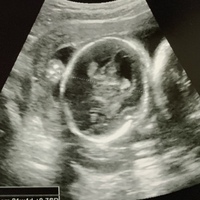

チャーミー小結さんの妊娠17週目のエコー写真 命の始まりは神秘的! 2D・3D・4Dのエコー写真で見る「私と赤ちゃんの実録260日」 産科のある病院に転院して最初に撮ったエコー写真です。 これまでの写真と比べても、よく動き回っているのが分かります 17週5日で検診を受けてきたのですが、 赤ちゃんの頭が2週分近く大きく 434mmありました。 FLは28mmでこちらも週数よりは少し大きめのなのですが、 頭が大きいとダウン症の可能性があると 聞くので不安です。 内臓には何も問題はありませんでした。 12週の頃のNTは18mm 私は36歳の経産婦です。 頭 32週0日に対して、推定予定日33週6日。 推定体重は2,227gです。 +1w6dなので、 前回の検診よりも成長は落ち着いているみたいですね。 大きくなった原因は? 赤ちゃんが巨大化する原因は、大きく分けて二つあるそうです。

医師監修 妊娠17週のエコー写真を多数掲載 みんなのエピソードつき Michill ミチル

妊娠17週 赤ちゃんのエコー写真 超音波写真まとめ たまひよ

妊娠17週目エコー写真 胎児の大きさ 胎動や性別が分かることも 妊娠中期 All About